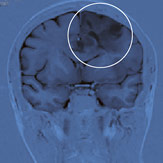

Abb. 4

Das MRI nach der Operation zeigt die weitgehend radikale Entfernung des Tumors.

Unter Schonung der definierten funktionellen Gebiete wurde der Tumor behutsam entfernt. Die anschliessende intraoperative Ultraschalluntersuchung zeigte kein tumorähnliches Gewebe innerhalb des Gehirns, was später nach der Operation mittels MRI-Untersuchung bestätigt wurde (Abb. 4). Zusätzlich zur Ultraschalluntersuchung wurde im Operationssaal eine zweite Elektrokortikographie angefertigt, die keine Krampfaktivität auf der Hirnoberfläche mehr zeigte.